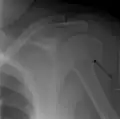

Multi-fragmented, or comminuted fracture of the proximal humerus with involvement of the greater tuberosity -

Proximal humerus fracture -